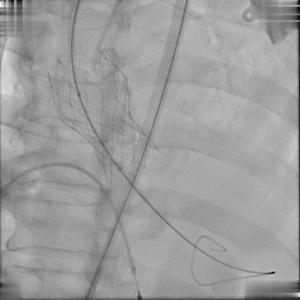

患者突发心脏停跳,紧急进行人工按压等急救措施;尝试予以冠脉保护,并在停跳状态下,快速植入Edwards Sapien 3球扩瓣;

尝试冠脉保护

瓣膜定位释放

再行数十秒心脏按压,患者心脏恢复跳动、血流动力学状态恢复正常,即刻跨瓣压差为零,顺利结束手术。

即刻植入效果